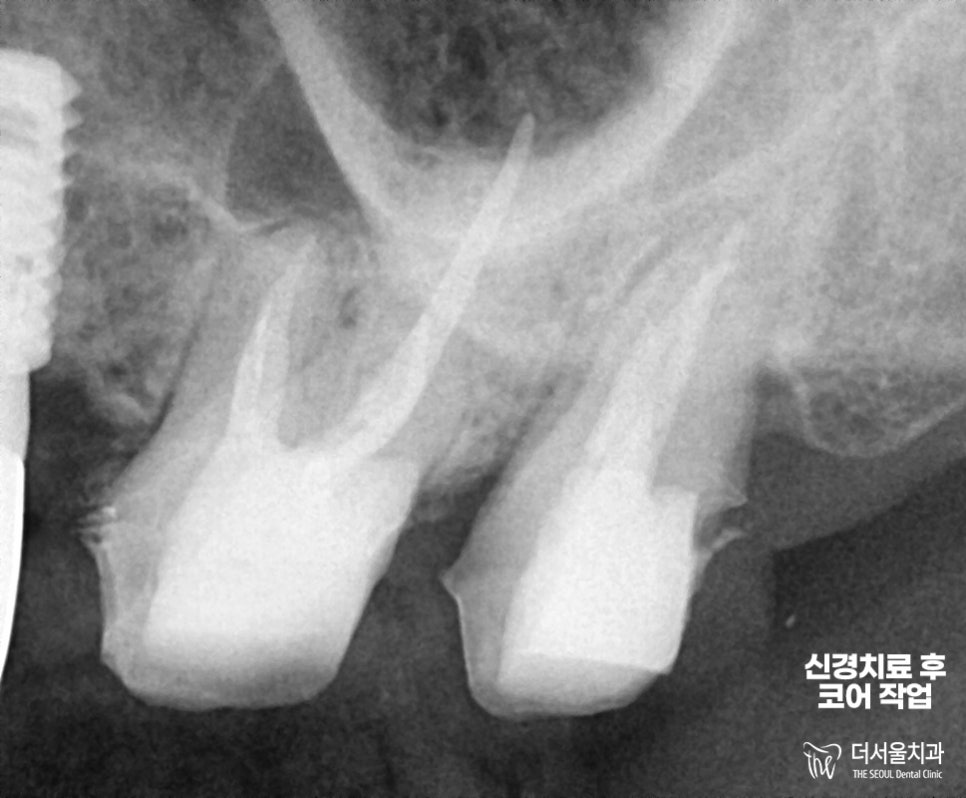

남은 부분은 성남 치과의원 에서

레진 재료로 👉코어 작업을 끝마쳤습니다.

크라운 보철 제작이 완료되기 전,

임시 치아 를 씌워드려서

일상 생활에 지장없도록 해드렸습니다.